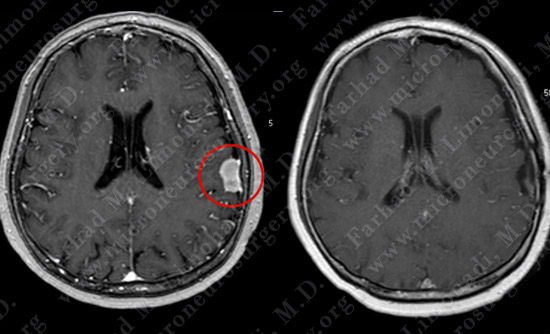

Post-op Imaging

Before Operation                                                 After Operation

Post-op MRI shows complete resection of the tumor with no injury to surrounding neurovascular structures.